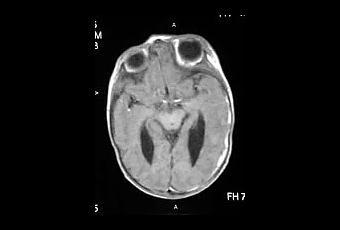

Es la dilatación del sistema ventricular del cerebro debido a un proceso

obstructivo, ya sea infeccioso, inflamatorio, neoplasico o extraventricular que impide el flujo normal

del liquido cefalorraquídeo entre el 3er y 4to ventrículo, o en la fosa

posterior del 4to ventrículo. La ventrículomegalea afecta el 0,5 de cada 1000

El diagnostico se realiza mediante ecosonografia fetal, tomografía craneal o

resonancia cerebral y su tratamiento siempre va a depender de la causa,

generalmente se utilizan analgésicos, esteroides, antibioticoterapia y

procedimientos quirúrgicos específicos.